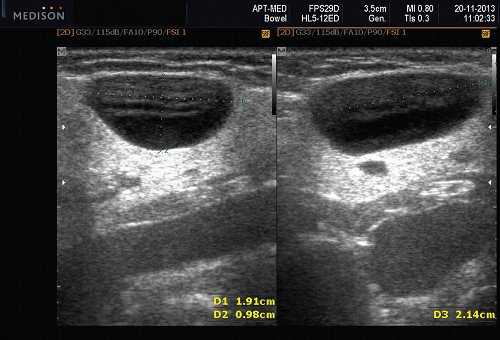

При этом определяли структуру, размеры желез в длину, толщину, ширину, их объем. Дополнительно, для уточнения количественных параметров кровотока в крупных и мелких сосудах околоушных желез, применяли метод ультразвуковой допплерографии.

- ультразвуковой метод (является наиболее доступным, безопасным и информативным в процессе дифференциальной диагностики патологического состояния слюнных желез).

Рис. 5. Камень протока поднижнечелюстной слюнной железы.

Рис. 6. Камень в паренхиме поднижнечелюстной слюнной железы.

Рис. 7. Камень в протоке поднижнечелюстной слюнной железы.